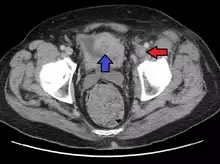

Deep vein thrombosis of the left external iliac in a person with bladder cancer resulting in this condition.